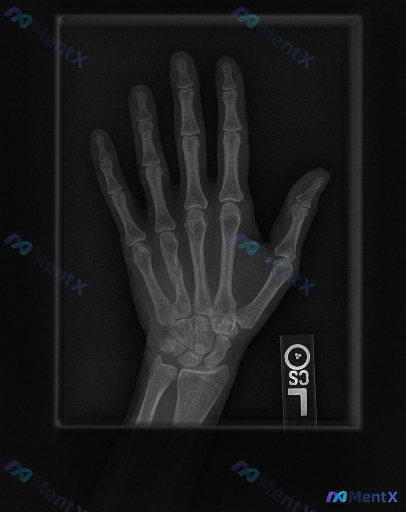

整理到一份左手正位X光片的影像资料与临床背景: 影像表现概要 - 诸掌骨、指骨、腕骨骨皮质连续,未见明确骨折线、脱位或明显骨质破坏; - 各关节间隙宽度大致正常,关节对位良好,未见明显退行性变; - 拇指掌指关节尺侧可见一枚圆形边界清晰的高密度影,报告考虑为生理性籽骨; - 软组织影轮廓尚自然,未见...